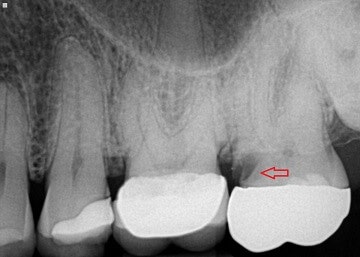

위 엑스레이 사진의 빨간 화살표를 보시면 검정색 부분이 있습니다. 이게 바로 2차 충치입니다. 엑스레이 사진에서 검은색 부분은 빈공간, 흰색 부분은 무언가 차있는 공간을 나타내는데요, 2차충치로 인해 크라운 아랫쪽이 비어있는 상태입니다. 이런 경우, 겉의 크라운이 버티지 못하고 파절되는 경우가 있습니다(출처: https://atlasdental.ca/)